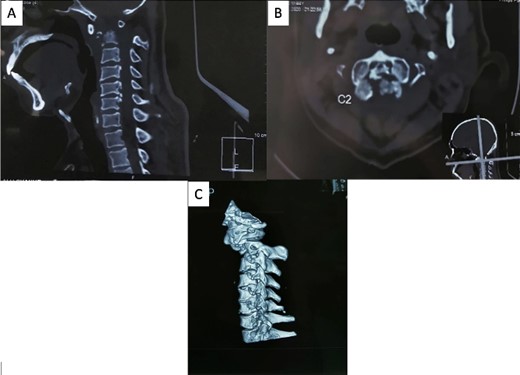

The patient reported sensory disturbances in all four extremities, particularly related to abnormalities in light touch, without any other sensory qualities being affected. A Cervical CT scan revealed a type III odontoid fracture, D’Alonzo type III, with atlantoaxial dislocation, fielding grade 3, and ossification of the posterior longitudinal ligament on the C4-C6 levels (Fig. 1). Cervical MR imaging showed cervical canal stenosis at the C1-C2 level due to atlantoaxial dislocation (Fig. 2). Consequently, we planned to proceed with stabilization surgery. We were unable to perform angiography on this patient due to limited facility resources for such examinations.

(A) Sagittal MRI showed significant compression on the occipitocervical junction due to atlantoaxial dislocation with blockage from (B) MR myelography.